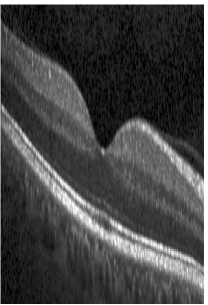

Fig. 4 shows samples drawn from p(b)𝑝𝑏p(b), modeling fovea-centered 3-D volumes (left) and circular scans (right). Additionally, as supplementary material we provide a video that visualizes the relevance of each component of W𝑊W exemplary for the 3-D setup, like translation, rotation, thickness of layers or position and form of the fovea.

Refer to caption

(a)

(b)

(c)

(d)

Figure 4: Samples generated by the shape prior distribution p(b)𝑝𝑏p(b) trained on volumes (left) and circular scans (right). Only one half of the volume is shown.